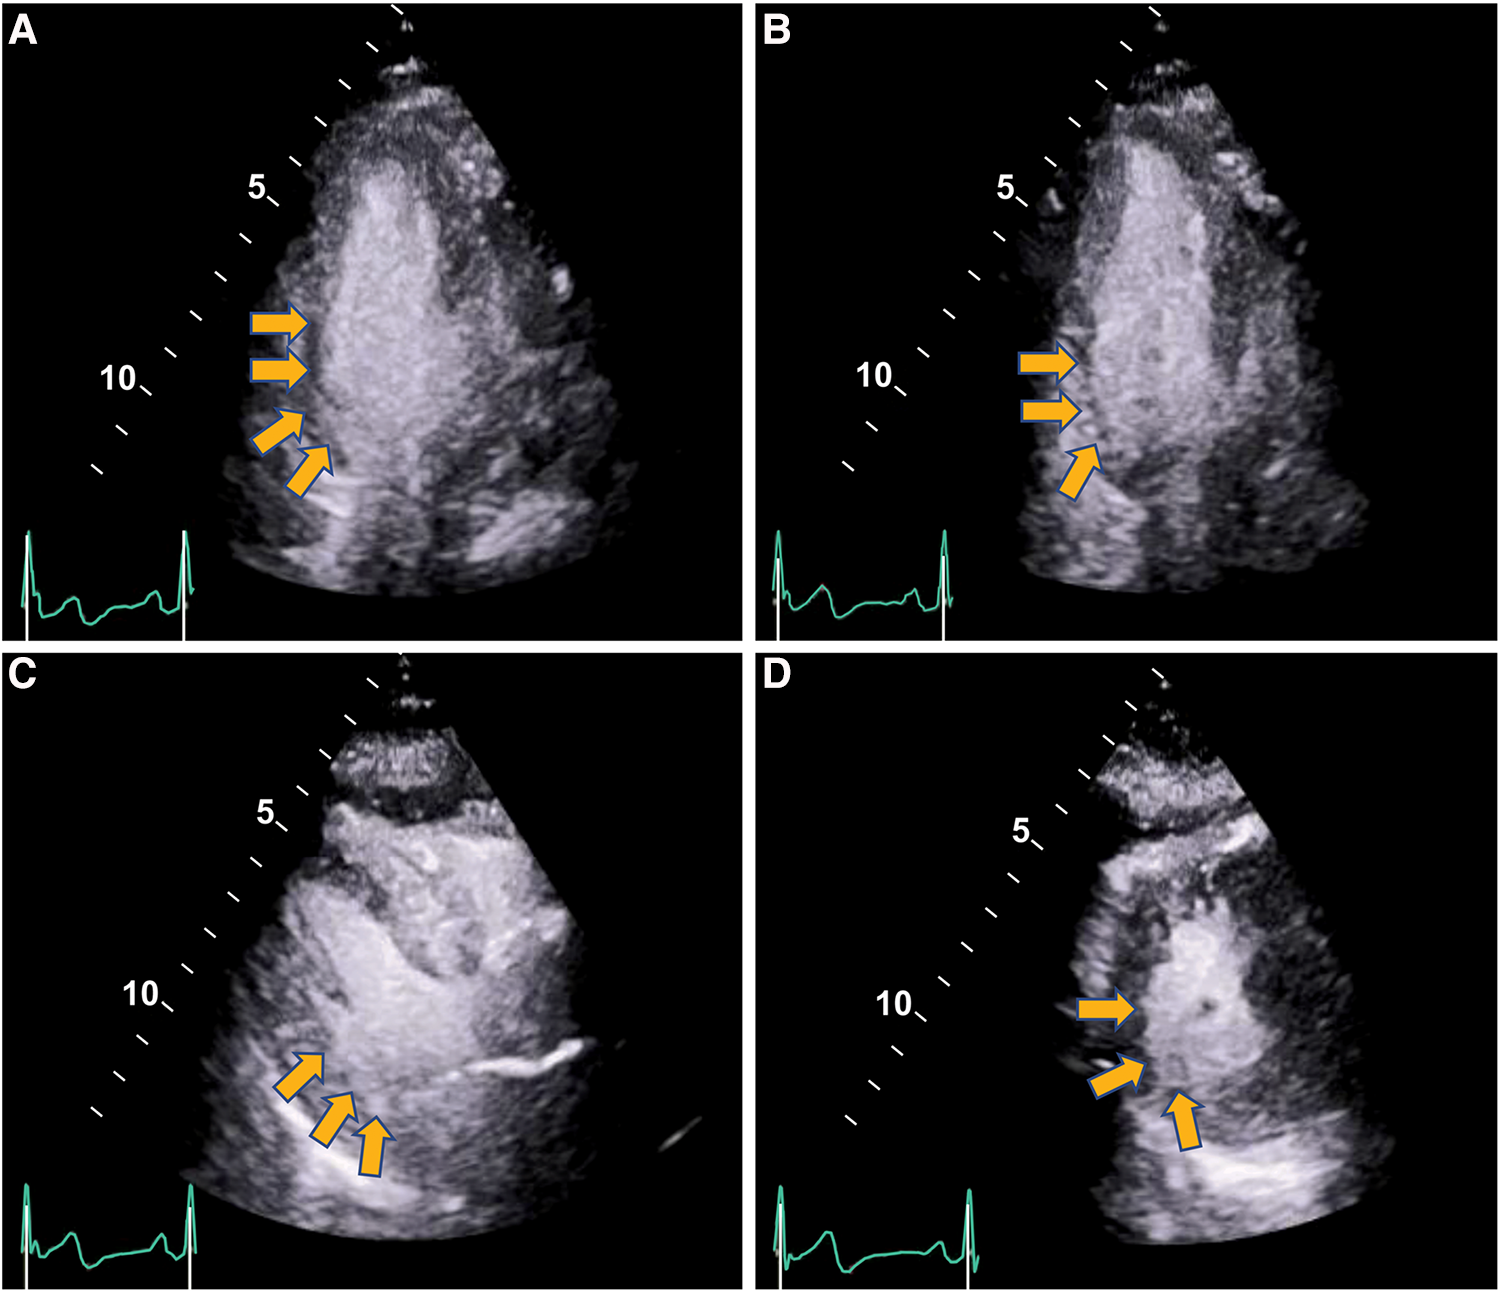

The care team made the clinical decision to proceed with cardiac stress testing for further risk stratification. Within 15–30 s of the initiation of exercise, the patient started to notice phantom odor perception which was not observed by the staff standing around the patient; this was immediately followed by ECG changes of significant ST elevations in the inferior leads with reciprocal changes in leads I, aVL and V1-2 (Figure 1), associated with chest discomfort and shortness of breath. The test was instantly aborted, and the patient was assisted back to a supine position. Echocardiography images were obtained immediately showing new left ventricular regional wall motion abnormalities that were concordant with the electrocardiographic changes (Figure 2, Supplementary Video S1). The ST elevations resolved within 40 s, and repeat echocardiographic images also showed resolution of the regional wall motion abnormalities. This was shortly followed by another similar self-limited episode of transient ST elevations on ECG associated with anginal symptoms. Owing to ECG changes concerning for acute coronary plaque rupture, the patient was transported emergently to the cardiac catheterization suite. Invasive coronary angiography showed sluggish flow in the right coronary artery but no obstructive epicardial coronary artery disease (Supplementary Video S2).

Figure 2

Regional wall motion abnormalities with severe hypokinesis of the basal infero-septal, basal, and mid inferior and infero-lateral segments seen on stress echocardiography during anginal episode (yellow arrows) (end-systolic frames shown). Panel (A) Apical 4-chamber. Panel (B) Apical 2-chamber. Panel (C) Parasternal long axis. Panel (D) Parasternal short axis. (Supplementary Videos S1, S2).